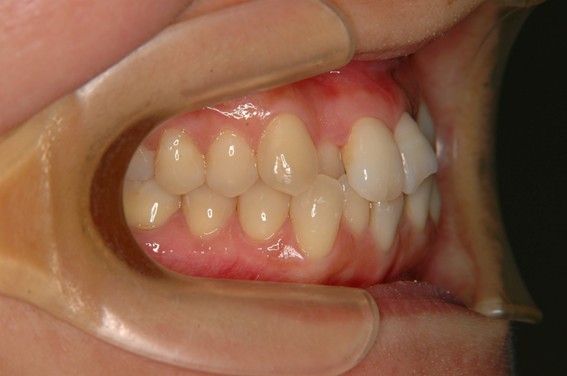

| 主訴 | 前歯が逆に噛んでいる。 |

| 治療内容 | 表側ワイヤー矯正、ジルコニア補綴を行いました。 |

| 治療費 | ワイヤー矯正660,000円(税込) ジルコニア176,000円(88,000円×2歯)(税込) |

| 治療期間 | 30ヶ月 |

| 治療回数 | 30回 |

| 想定されたリスク | 歯根吸収、歯髄壊死、歯髄充血、歯肉退縮のリスクがありました。 |

骨格性Ⅲ級・前歯部反対咬合の症例でした。反対咬合のまま治療していた前歯のサイズ不調和を、表側ワイヤー矯正とプロビジョナルクラウンで調整。正中を整え、犬歯・臼歯ともⅠ級、適切なオーバージェット(上下前歯の前後的な距離)・オーバーバイト(上下前歯の垂直的な重なり)に仕上げました。